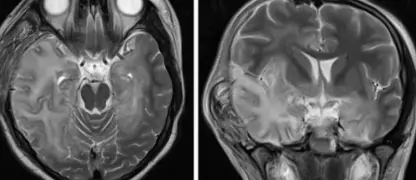

Image description of Viral Encephalitis

Viral encephalitis is a serious condition where a viral infection causes inflammation in the brain. It can range from mild to life-threatening, requiring early detection and treatment.